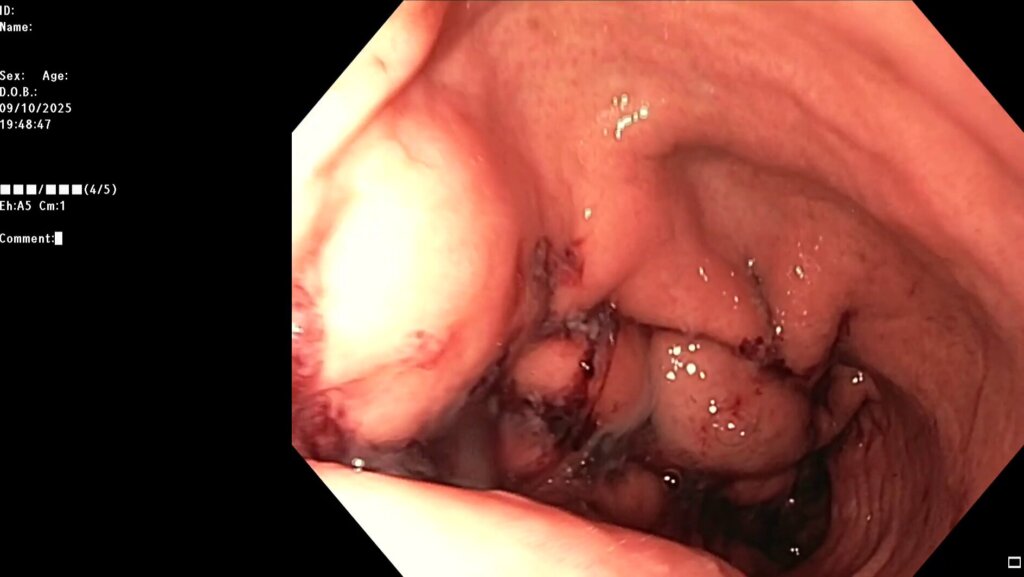

После предварительного обследования произведена операция: ESG + АПК (APC) свода; всего использовано 6 швов, время процедуры ≈ 120 минут.

Комбинированный метод представляет собой эндолюминальное ушивание желудка (формирование «рукава») с добавлением локальной аргоноплазменной коагуляции (АПК, APC — поверхностная неконтактная термальная абляция слизистой) в зоне свода желудка с целью индуцирования контролируемого фиброза и снижения секреции грелина. ESG выполняется перорально под визуальным контролем с использованием системы Overstitch;

В первые 2-4 суток — вечерний субфебрилитет до +37,4°C; лабораторно — умеренный рост ЦРБ и лейкоцитоз; продолжена антибактериальная и антисекреторная терапия на протяжении 7 дней; симптомы купированы, лабораторные показатели пришли в норму.

Клиническая интерпретация: течение соответствует описанным в литературе ранним реакциям на подобные вмешательства и термическую абляцию; пациент продолжает мультидисциплинарное наблюдение. За 2 недели сброс веса составил 5% от общей массы, через месяц потеря веса 8% от общей массы, через 2 месяца — 12%, через 3 месяца — 17%.